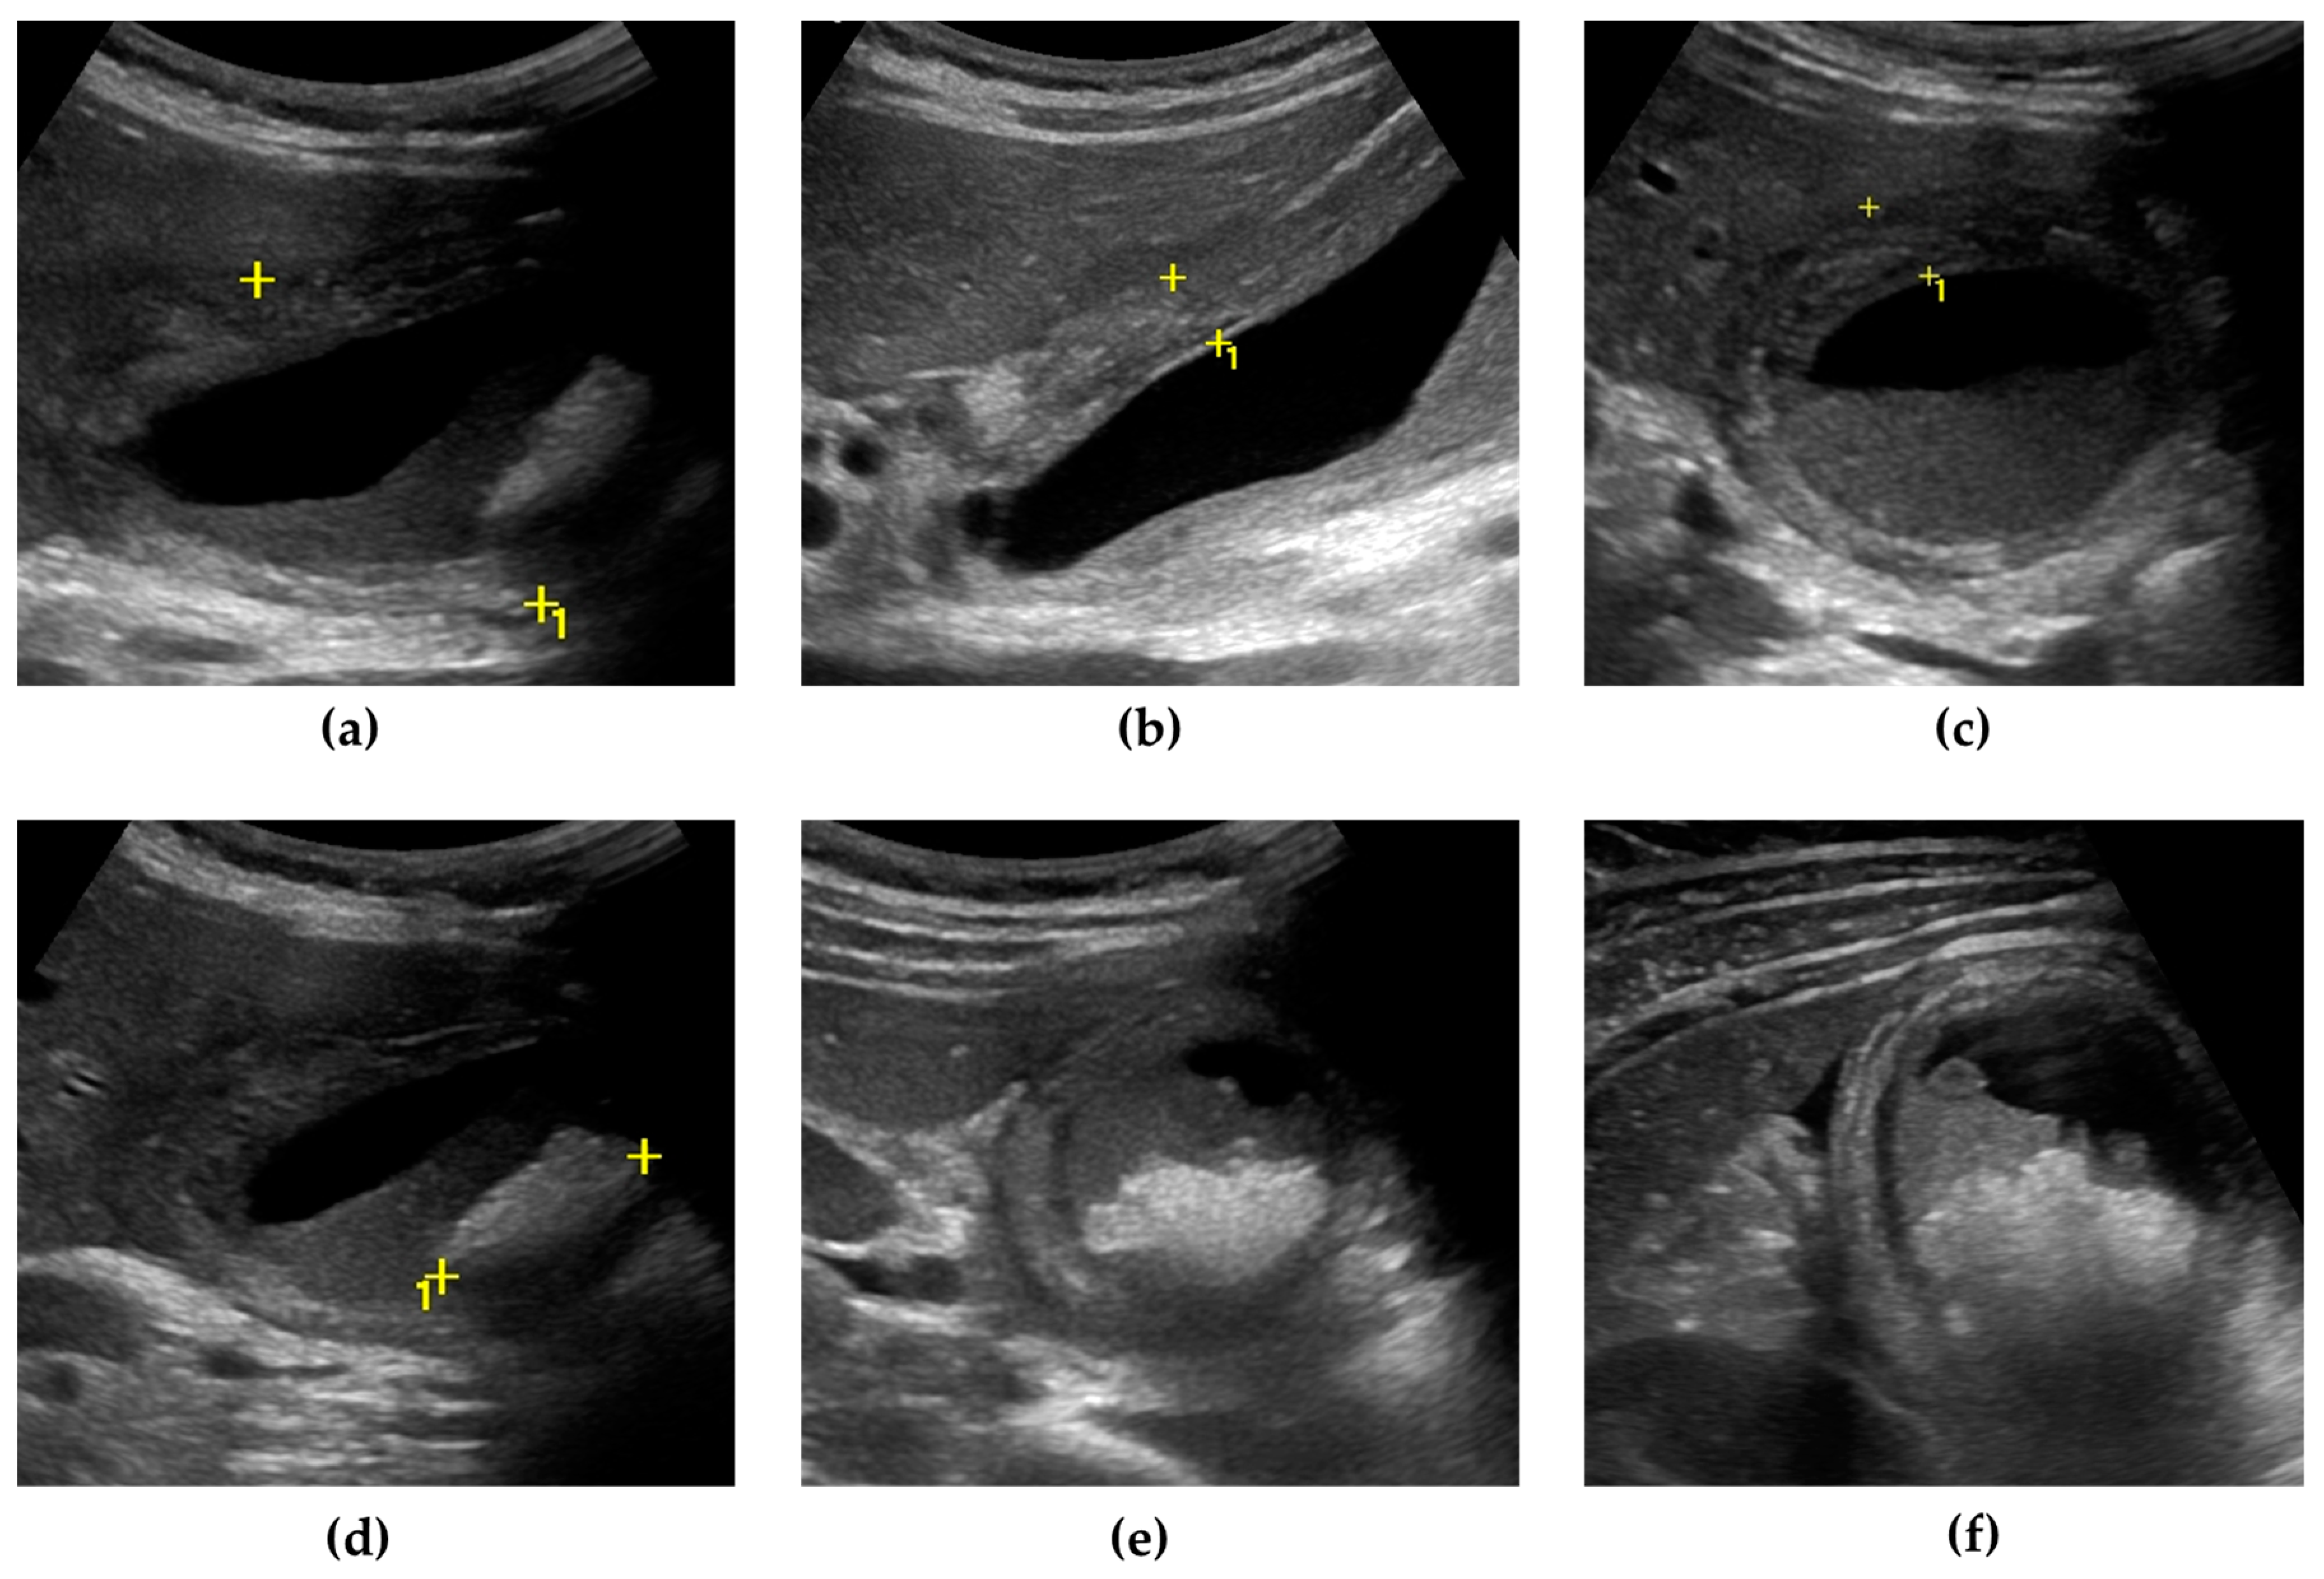

+ **Ultrasound first**: **85%** sensitive for cholecystitis, appendicitis

+ **CT if ultrasound negative**: **98%** sensitivity for most pathology